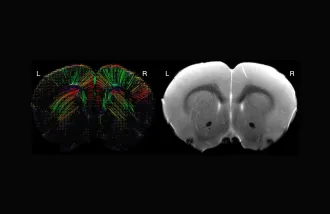

Exploring MRI's role in neuroscience research on model organisms

Recognizing the potential for wider application in small-animal neuroscience research, the Neurosciences Preclinical Imaging Lab (NPIL) at Wu Tsai Neuro hosted its 3rd annual symposium and named the recipients of its Pilot Grants.